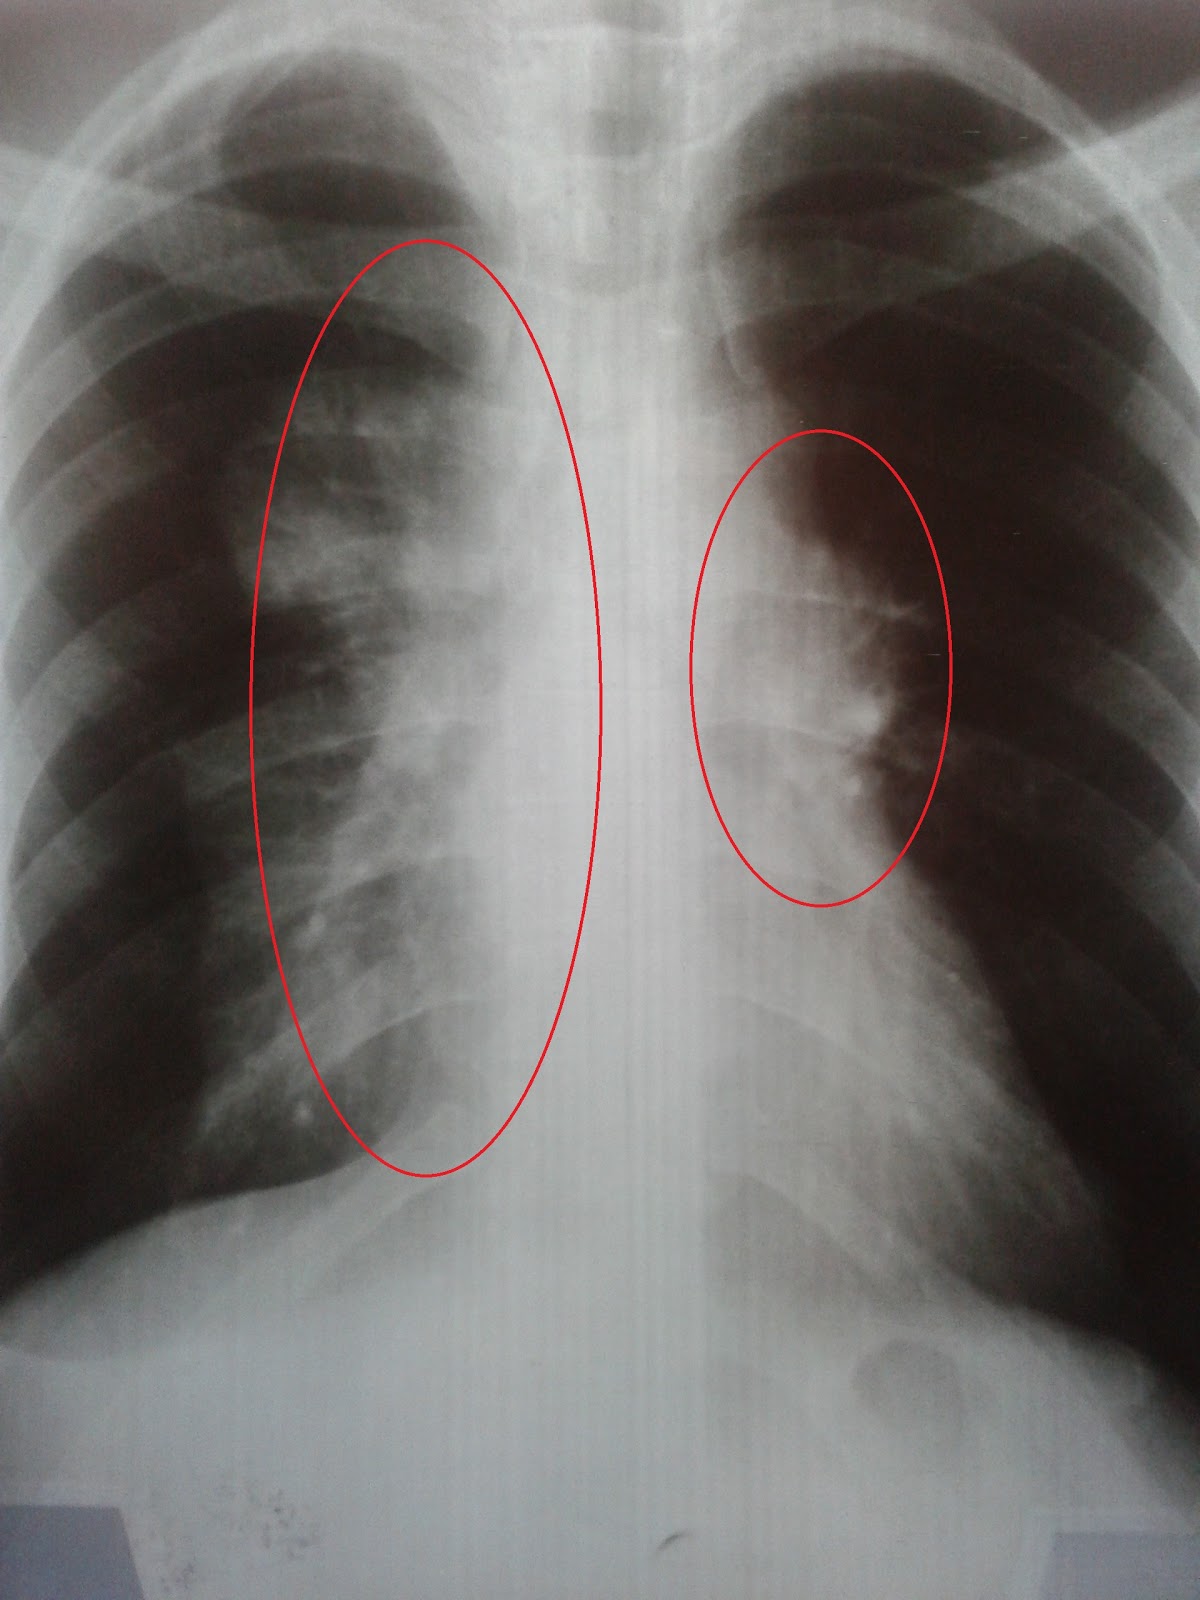

Esta é a ultima radiografia, feita no dia 23 de outubro, a área circundada em amarelo é só pra mostrar que o cateter aparece no raio-x. ai é onde esta passando o cano do Jarvs. Não existe mais as áreas brancas, o pulmão esta excelente , nem sinal dos tumores.